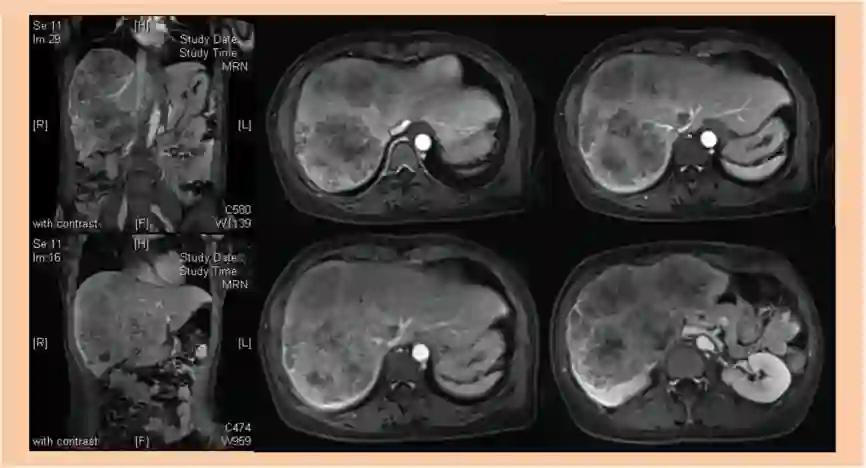

2017-11-03 肝脏MR增强:肝右叶及左内叶见多发团状异常信号影,较大者位于V及VI段,大小约13*7cm,病灶信号不均。增强后病灶呈边缘强化。肝IV段另可见一类圆形长T1长T2信号影,大小约2.9*1.9cm。考虑转移瘤。

1. 该患者诊断为结肠癌伴多发性肝转移,肝脏MR增强示肝右叶及左内叶可见多发团状异常信号影,考虑为转移瘤。较大者位于V及VI段,大小约13*7cm,肿瘤病灶大,负担重,转移瘤肝转移灶初始不可切除